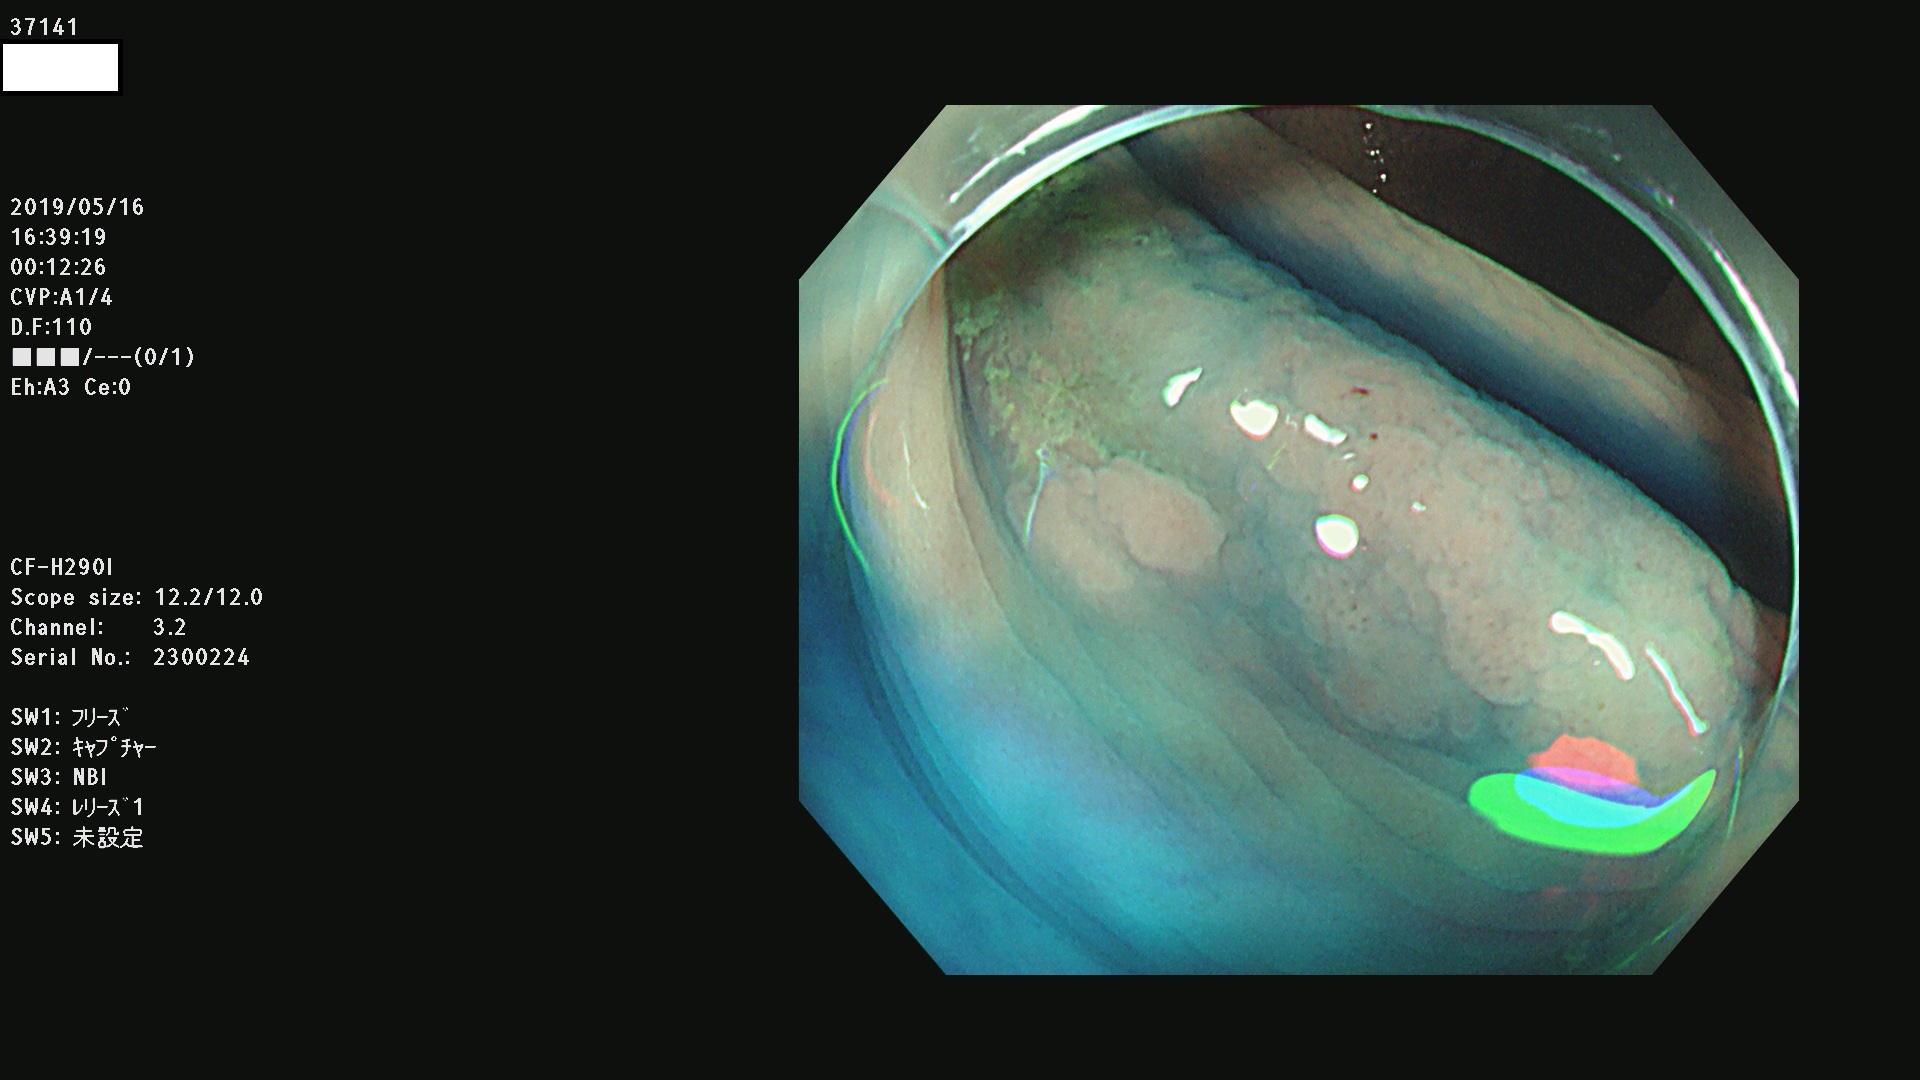

37100 37101 37102 37104 37106 37108 37110 37111 37112 37113 37115 37118(SSAPのみ) 37120 37122 37123 37124 37127(SSAPのみ) 37128(SSAPのみ) 37131 37132 37133 37134 37135 37139 37141 37142 37143 37144(SSAPのみ) 37145 37147(SSAPのみ) 37148 37149 37150 37153 37154 37157 37159 37161 37162 37163 37164 37165 37166 37167 37168 37169 37170 37171 37172 37173 37175(SSAPのみ) 37176 37177 37178 37180(SSAPのみ) 37181 37184 37185 37186 37187 37188 37189 37190 37192 37194 37197 37198

発見困難で危険性の高い平坦型病変(上記100名より抽出)